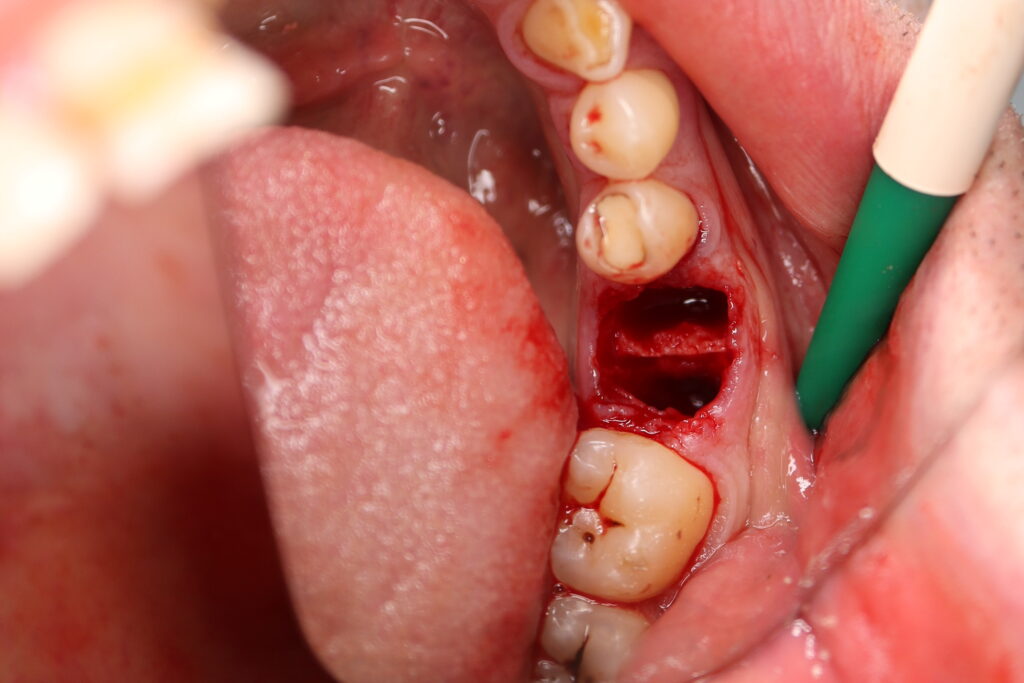

хирургический этап

Это фото может содержать тяжелый для восприятия контент